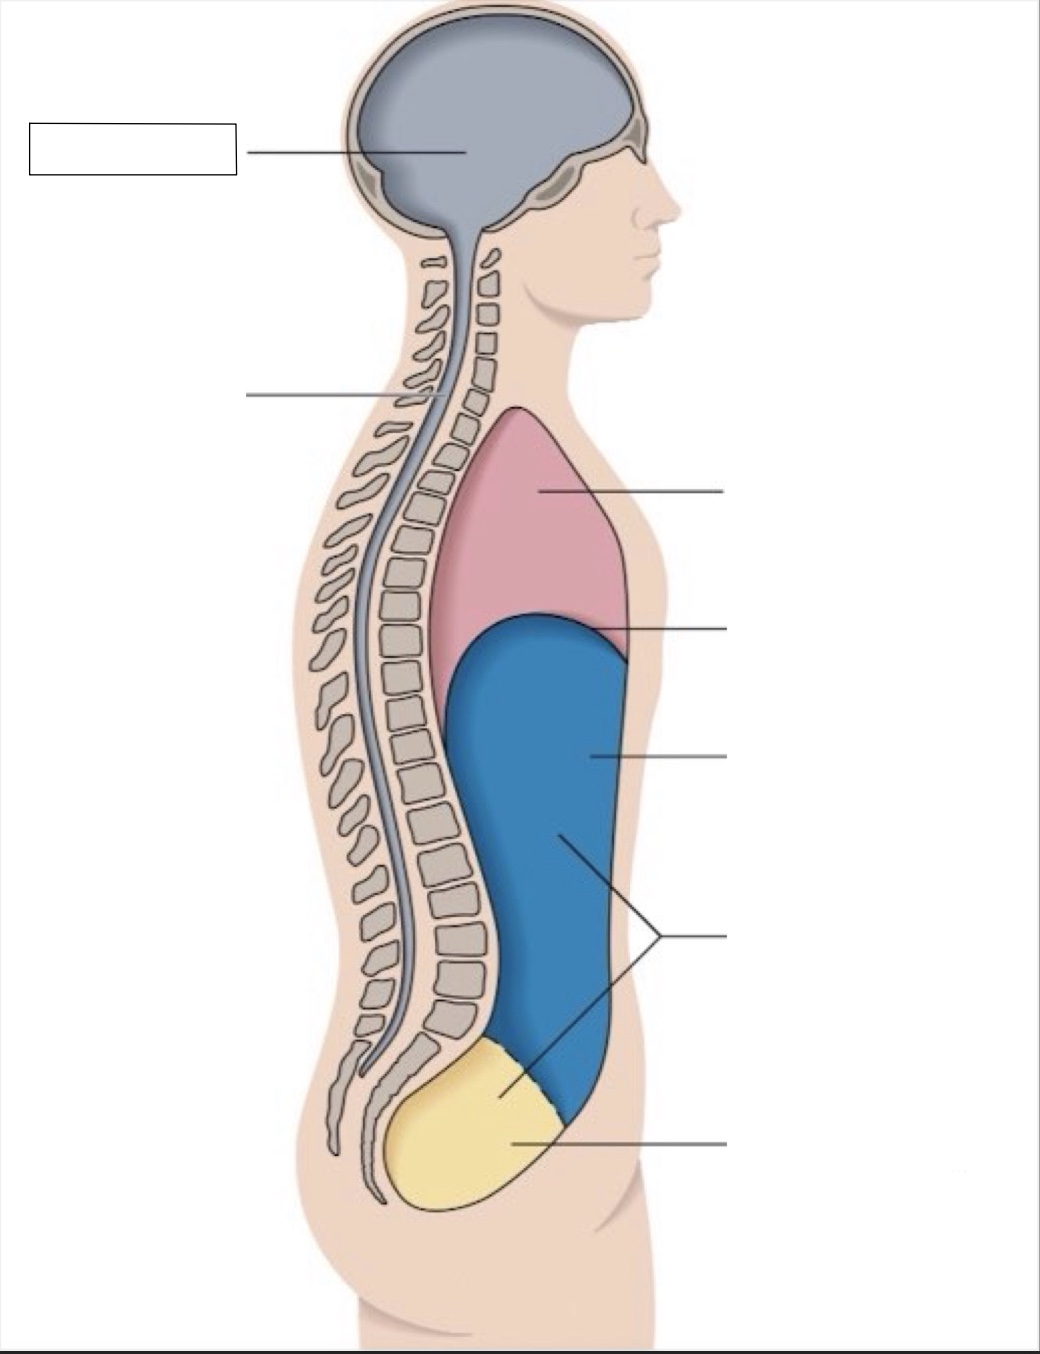

thoracic cavity

diaphragm

abdominal cavity

abdomino-pelvic cavity

pelvic cavity

spinal cavity

cranial cavity